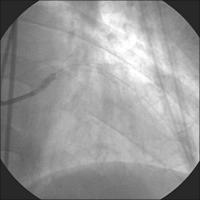

Linke Koronararterie LAO/Kaudalprojektion

Abbildung 2

Keywords: Arteria coronaria sinistraKardiologieKoronarangiographie